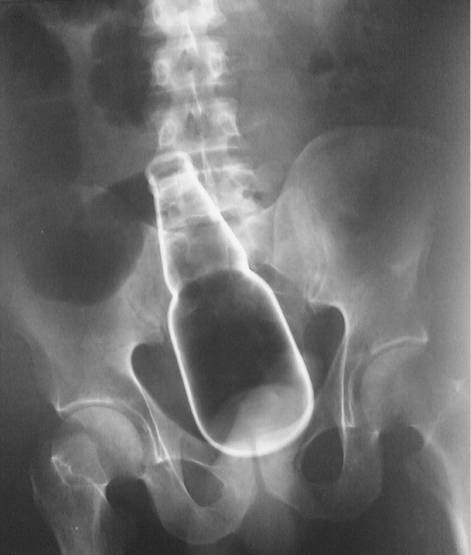

7、危险的肛塞

35岁男性因直肠出血和腹痛被送进急诊。

查体发现腹部有异物,但是无外伤。直肠指检发现异物但是无法看到。患者生命体征平稳之后进行X光片检查,情况如上图……

外科手术取出啤酒瓶之后给予抗生素和镇痛药物,患者恢复良好出院。

从肛门塞入异物然后取不出来的其实不少。这个病例发表在2010年的扭英上。